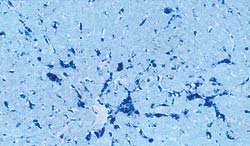

Technique "d'hybridation in situ" - Foie.

Présence de génome de PCV2 majoritairement dans le cytoplasme des cellules de Kupffer. |